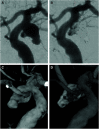

Figures